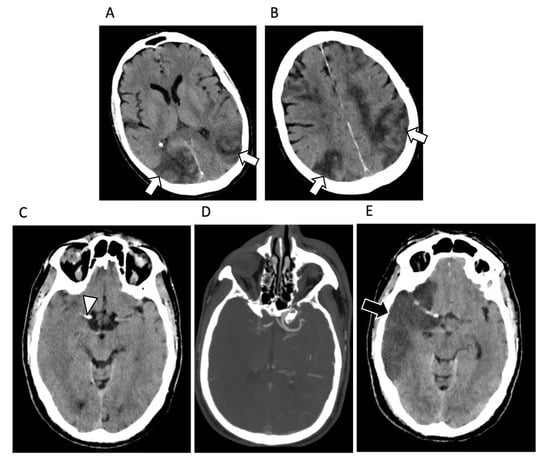

4. Central Nervous System Involvement